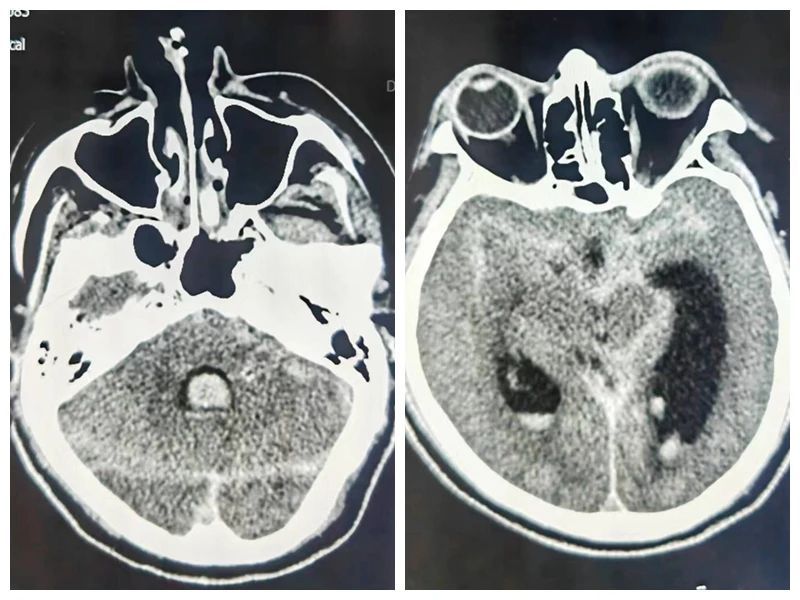

立即行CT检查

患者头颅CT可见广泛的蛛网膜下腔出血及脑室积血